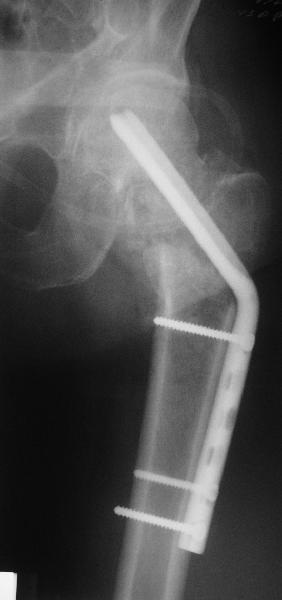

Re: Нелеченный перелом шейки бедра

Приветствую всех. Спасибо за активное участие в обсуждении. Выбрали вариант с остеотомией.

Снимки в приложении.